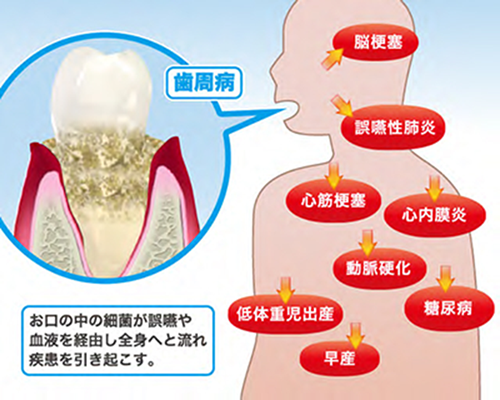

くっついていると、顎関節に負担がかかって顎関節症になるリスクが生じるばかりでなく、歯周病の増悪因子や、歯根破折(歯が割れたりヒビが入ってしまう)の原因にもなる事が分かってきました。TCHがある人は、日常から歯と歯を合わせないようにすることが大切です。